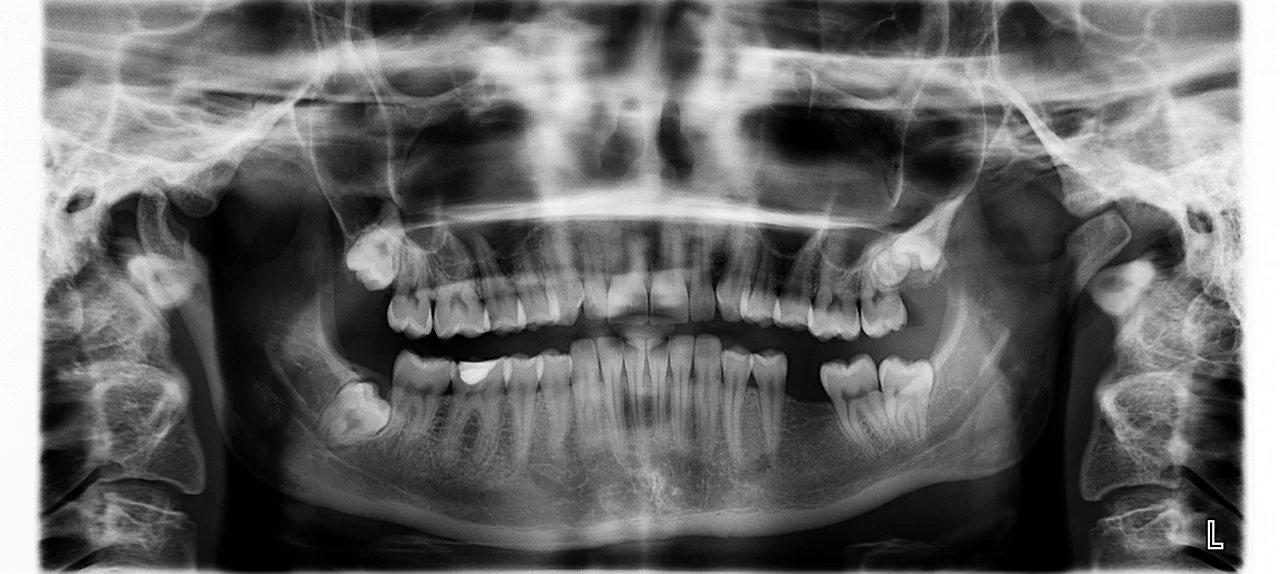

Radiografía Periapical

En nuestra clínica, la Radiografía Periapical se realiza utilizando tecnología de imagen digital de última generación. Priorizamos tu seguridad y comodidad, por lo que empleamos equipos de última generación que ofrecen una dosis mínima de radiación, mucho menor que los métodos tradicionales. Este enfoque personalizado nos permite obtener imágenes detalladas y de alta calidad de tus dientes y huesos maxilares, garantizando un diagnóstico preciso y rápido.